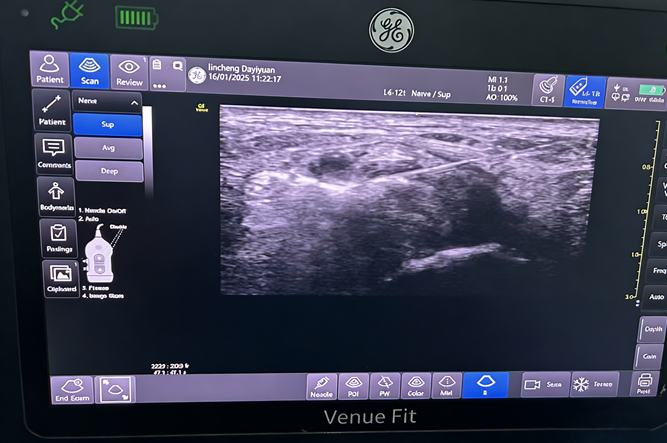

疼痛科王榆富主任团队凭借丰富经验,判断其为局部腱鞘囊肿,胫后神经损伤,果断为其施行了:抽取囊肿,周围神经射频脉冲调控治疗。